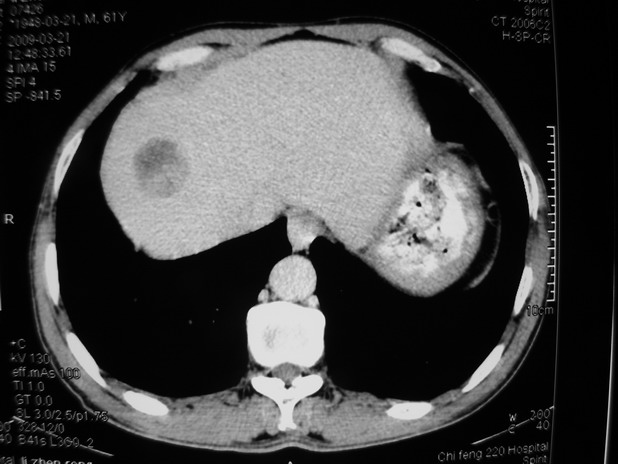

以下是引用余辉在2009-3-21 21:36:00的发言:[br]图像太乱了,建议楼主直接将强化数据按顺序列出来,病灶位置较表浅薄,有肝炎病史,灶内实性成分有显著强化,动脉期约60hu,考虑肝癌可能性大,进一步检查。